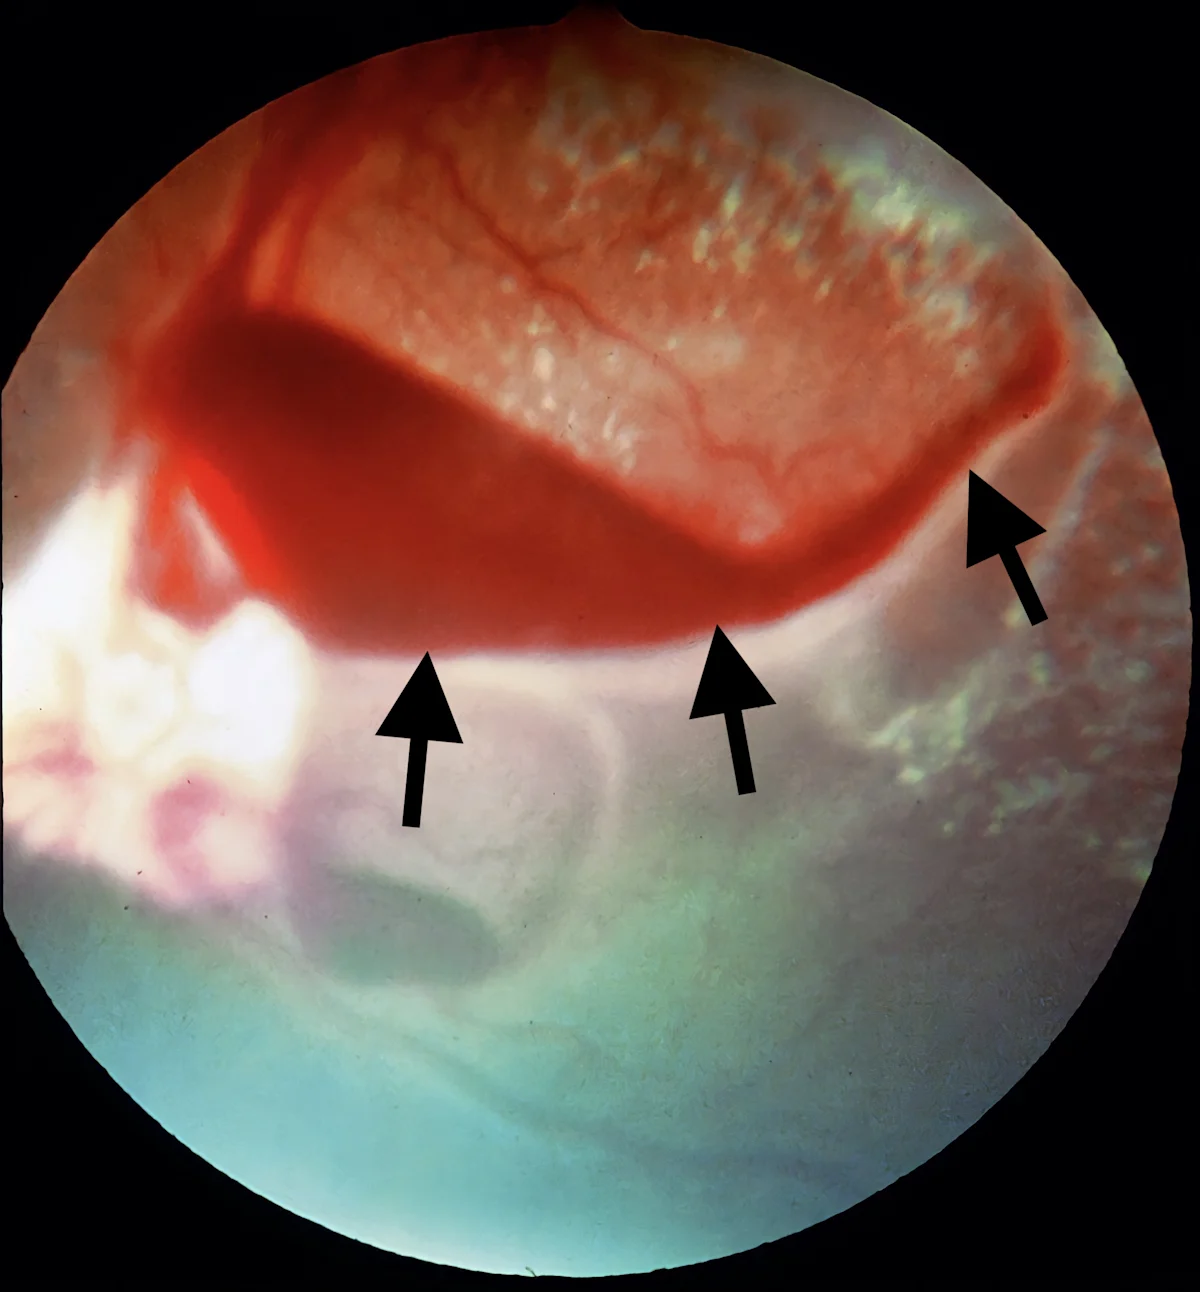

4. Retinal Detachment

Exudative or serous retinal detachment is common in patients with hypertension.11 Clear to yellow fluid accumulation or blood in the subretinal space that may appear as the retina billowing toward the examiner is characteristic during ophthalmoscopy (Figures 7 and 8). Retinal detachment can also be secondary to vascular, inflammatory, and/or neoplastic diseases of the retina, choroid, and retinal pigmented epithelium.12

Hazy appearance to tapetum shown and arrows pointing to distinct darker regions with prominent blood vessels.

FIGURE 8

Characteristic subretinal edema and billowing of the retina (arrows) associated with systemic hypertension in a cat

Leaking fluid can overwhelm the retinal pigmented epithelium pumping mechanism, causing fluid accumulation in the subretinal space and leading to retinal detachment and vision loss. Vision loss may be acute or gradual and partial or complete, depending on the degree of vitreal hemorrhage and retinal edema. Correction of the underlying cause may allow resorption of subretinal fluid; vision recovery is possible if the condition is treated before retinal ischemia occurs. Morphology of the retina and retinal pigmented epithelium interface may not recover, even after 6 months.13

Less likely differential diagnoses for retinal detachment are systemic infections (eg, fungal, bacterial [eg, ehrlichiosis, borreliosis], protozoal [eg, toxoplasmosis], viral [eg, FeLV, FIP, FIV]), neoplasia (eg, multiple myeloma, lymphoma), primary ocular conditions (eg, glaucoma), and immune-mediated conditions (eg, uveodermatologic syndrome, hyperviscosity syndrome secondary to multiple myeloma).